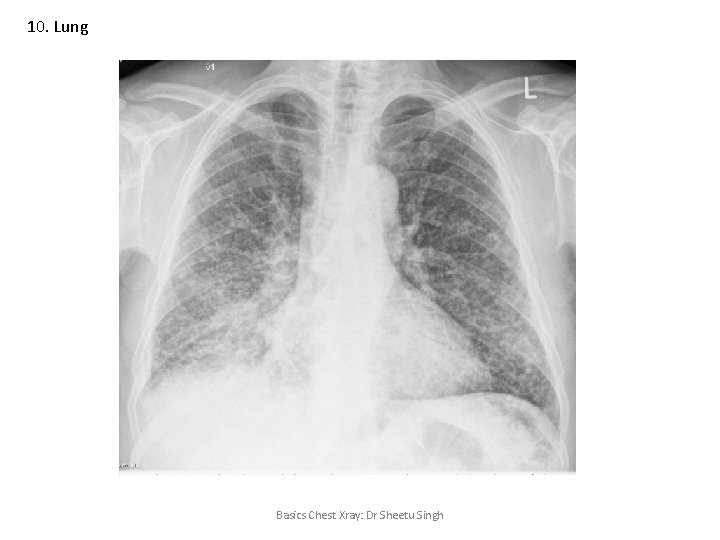

10. Lung Miliary shadows • • • Silicosis Coal workers pneumoconiosis Loeffler’s syndrome Sarcoidosis / Berryliosis Tuberculosis/Nocardia/Brucella Histoplasmosis Varicella Metastasis Rheumatoid arthritis nodules Wegner’s granulomatosis Amyloidosis Basics Chest Xray: Dr Sheetu Singh

10. Lung Basics Chest Xray: Dr Sheetu Singh